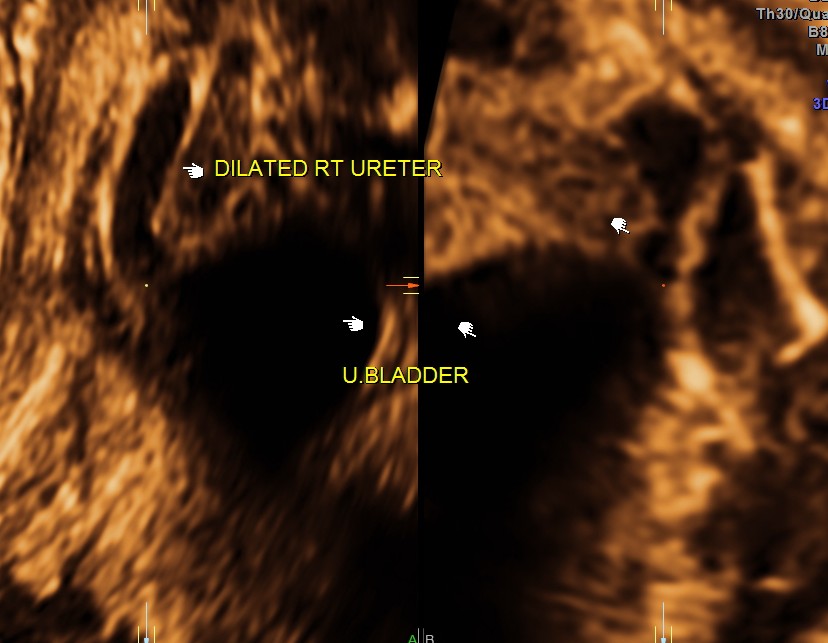

3 d reconstruction shows an echogenic tissue at the junction of ureter and bladder.

rendered image of the same